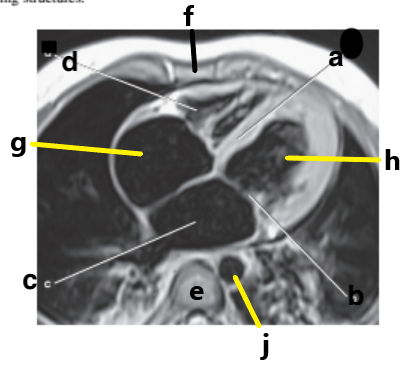

posterior cruciate ligament

Which letter is pointing to the posterior cruciate ligament?

e

What is letter G?

Right atrium

Which letter is pointing to the patellar ligament?

b

What is letter d?

medial collateral ligament

Which letter is pointing to the anterior cruciate ligament?

c